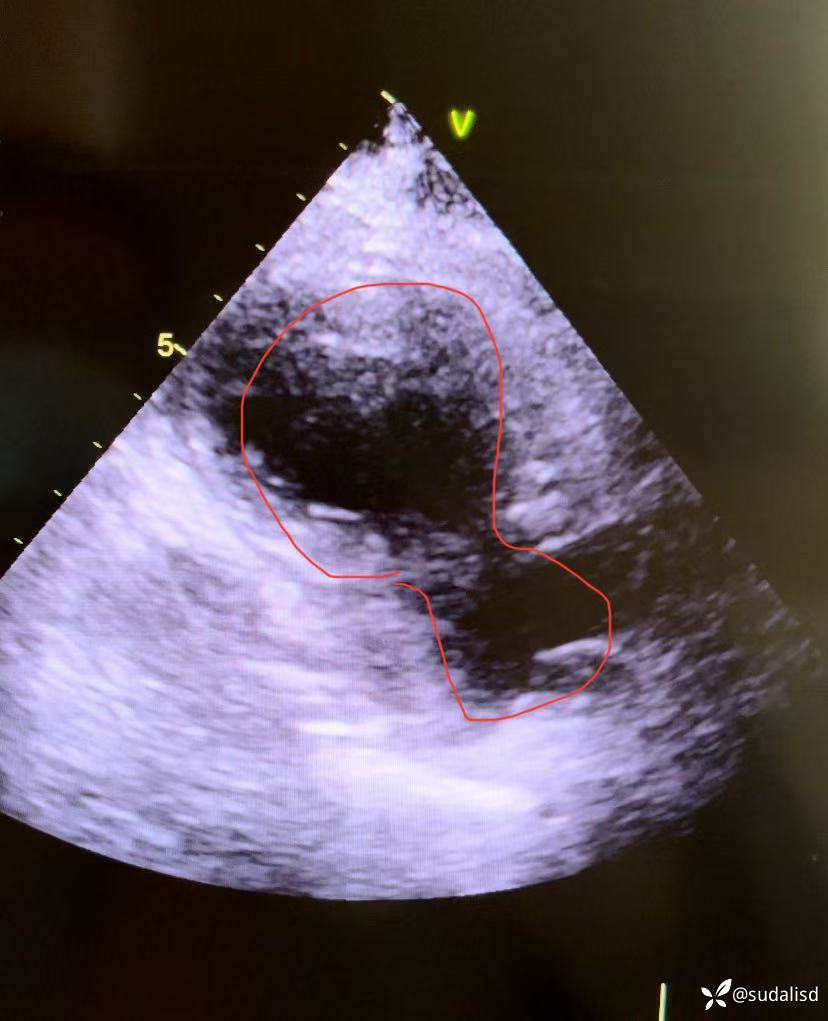

感谢我们医院心超室的叶医生每次都能打出漂亮的心尖球囊样改变的超声动图(即传说中北海道的“章鱼壶”样),让每例应激性心肌病都有一个完美的闭环。

第1例:2025.9.26骨科会诊的病例。83岁女性,腰椎术后+紧张焦虑诱发。再经典不过的应激性心肌病的心肌图(广泛T波倒置,胸导V3-V5的T波倒置最深,胸导II导的T波倒置最深,经典的指向心尖部的完美向量,秒杀),心超下的动图也是相当的经典的心尖球囊样改变(即传说中北海道的“章鱼壶”样)。其实这个病人4年前已经在我们科室发作过一次应激性心肌病,当时已经做了左室造影证实。这次是复发,自从广东省人民进修回来诊断的数十例应激性心肌病当中,第一次遇到复发的。